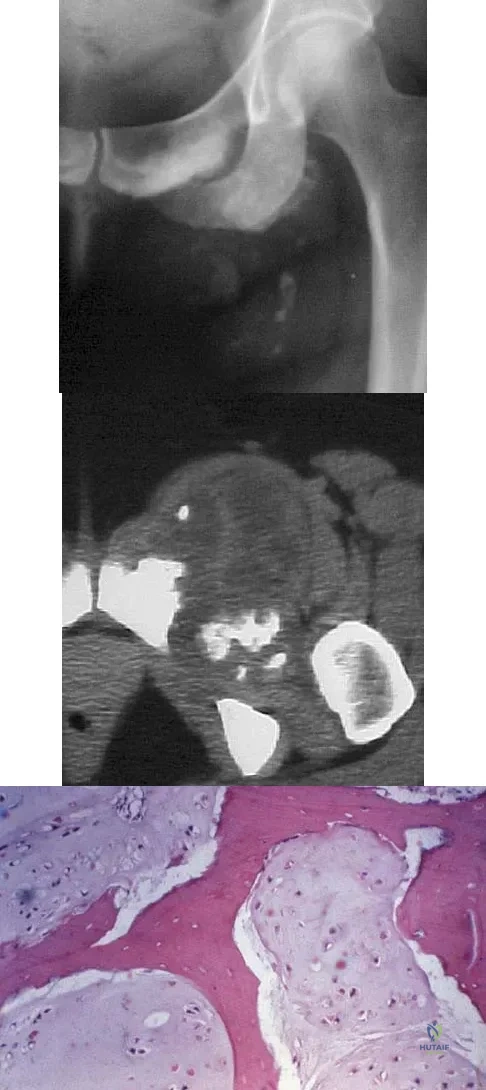

A 43-year-old woman has an enlarging mass in the left groin. A radiograph, CT scan, and a biopsy specimen are shown in Figures 42a through 42c. Treatment should consist of

A 10-year-old boy has a painful thigh mass. A radiograph, MRI scan, and biopsy specimen are shown in Figures 42a through 42c. What is the most likely diagnosis?